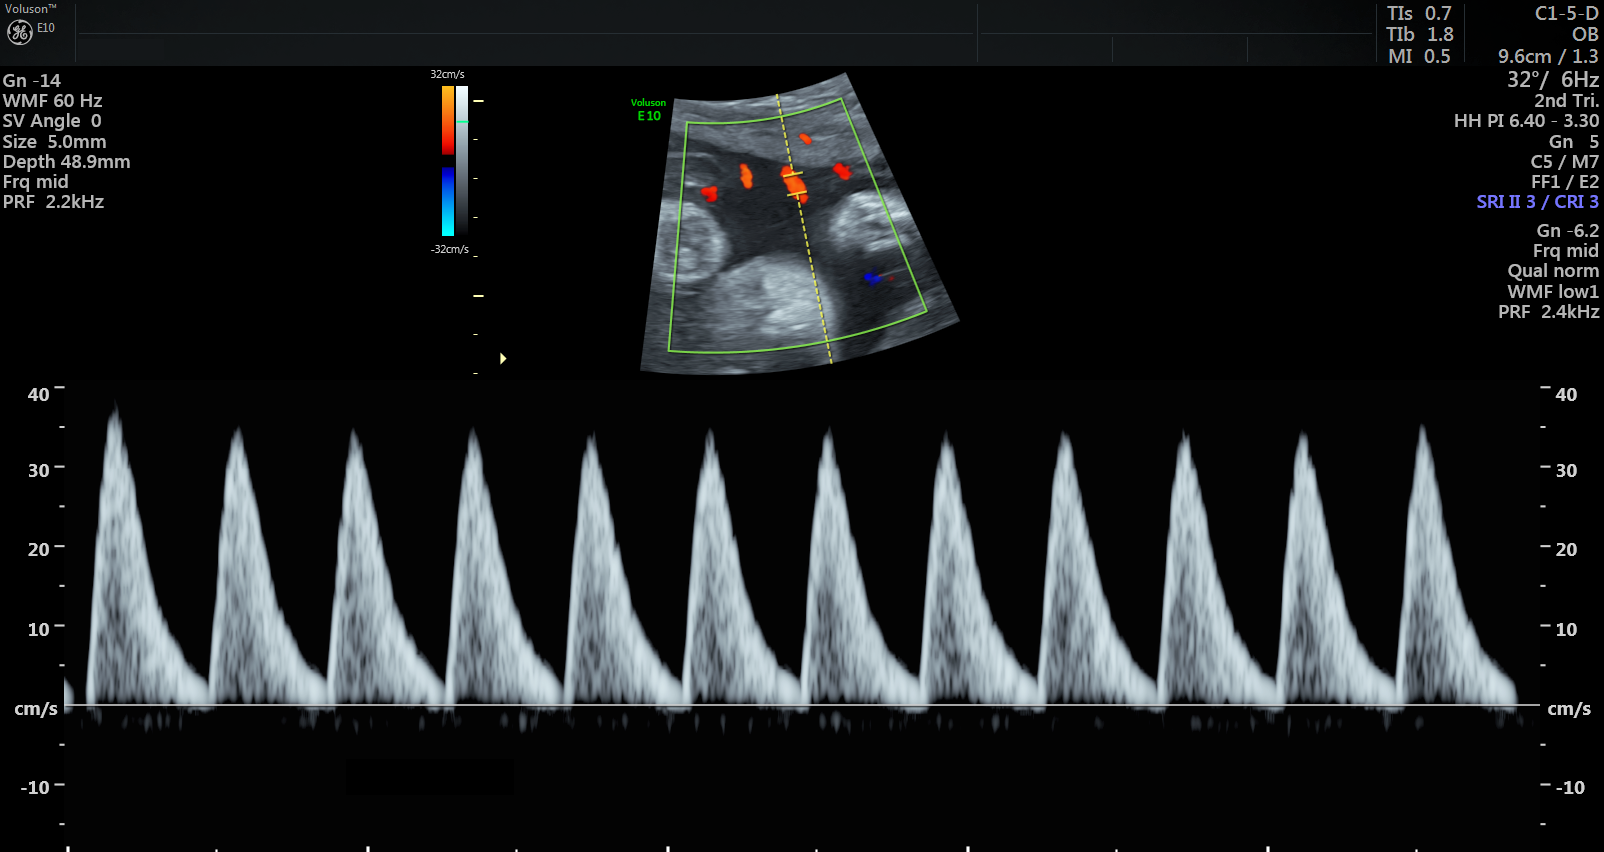

Currently, standard-of-care ultrasound scans measure blood flow at one point in the umbilical cord. The technique developed by Sled and his collaborators takes two measurements – one at the fetal end of the umbilical cord and one at the placental end. Sled says recording both measurements gives a much more accurate picture of the way blood is travelling through the umbilical cord.

“By looking at both measurements and the physics of how blood travels, we can get insight into how some of the finest blood vessels in the placenta are organized. The information this can provide to physicians is invaluable,” says Sled, who is also the Director of the Mouse Imaging Centre and a Professor and Vice-Chair in the Department of Medical Biophysics at the University of Toronto.

Animation showing where the new ultrasound technique measures blood flow along the umbilical cord. One measurement is taken at the fetal end and one is taken at the placental end.

The placenta has two blood circulations, one attached to the mother and another attached to the fetus. If the disease is primarily affecting the maternal circulation, it’s called maternal vascular malperfusion (MVM) and if the fetal circulation is primarily affected, it’s called fetal vascular malperfusion (FVM). MVM is the most common placental disease associated with fetal growth restriction, where a fetus is smaller than expected, and is often the cause of preventable stillbirth. FVM is less common but also associated with fetal growth restriction and other adverse outcomes.

The study recruited almost 430 women through Mount Sinai Hospital and Johns Hopkins Medicine. The researchers used their technique on the women’s ultrasound scans taken between the 26th and 32nd weeks of pregnancy. 241 women had their placentas physically examined after birth to verify diagnoses, which confirmed that 30 of these women had MVM and 16 had FVM, diagnoses that were successfully made with the ultrasound method.